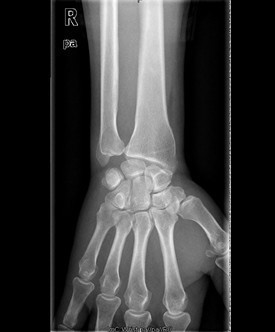

患者男,60岁,因“右腕部疼痛5月,右小指屈曲障碍20天”入院。入院前5月,患者无明显诱因情况下出现右侧腕部尺侧酸痛不适,未就诊治疗。左小指伸曲正常;入院前20天,患者出现右小指屈曲障碍,无小指指麻木,遂来我院治疗,门诊以“左小指深浅屈肌腱迟发性断裂”收入院。

查体:右侧小指伸直位,不能屈曲。右侧腕部尺侧可触及一质韧包块。右小指感觉正常,末梢循环正常。右小指不能主动屈曲掌指关节及中节、末节手指;伸指正常,余手指活动正常。 辅查:彩超示右腕包块处肌腱周围粘稠积液伴滑膜增厚。

初步诊断:右小指深浅屈指肌腱迟发性断裂 诊疗计划:择期行探查修复术

术中见右手小指屈指深肌腱探查修复术右手小指深浅屈肌腱陈旧性断裂、瘢痕形成,有粘连,邻近滑膜增生变性,右手小指、环指及中指屈指肌腱变性毛糙,有较多淡黄色积液。